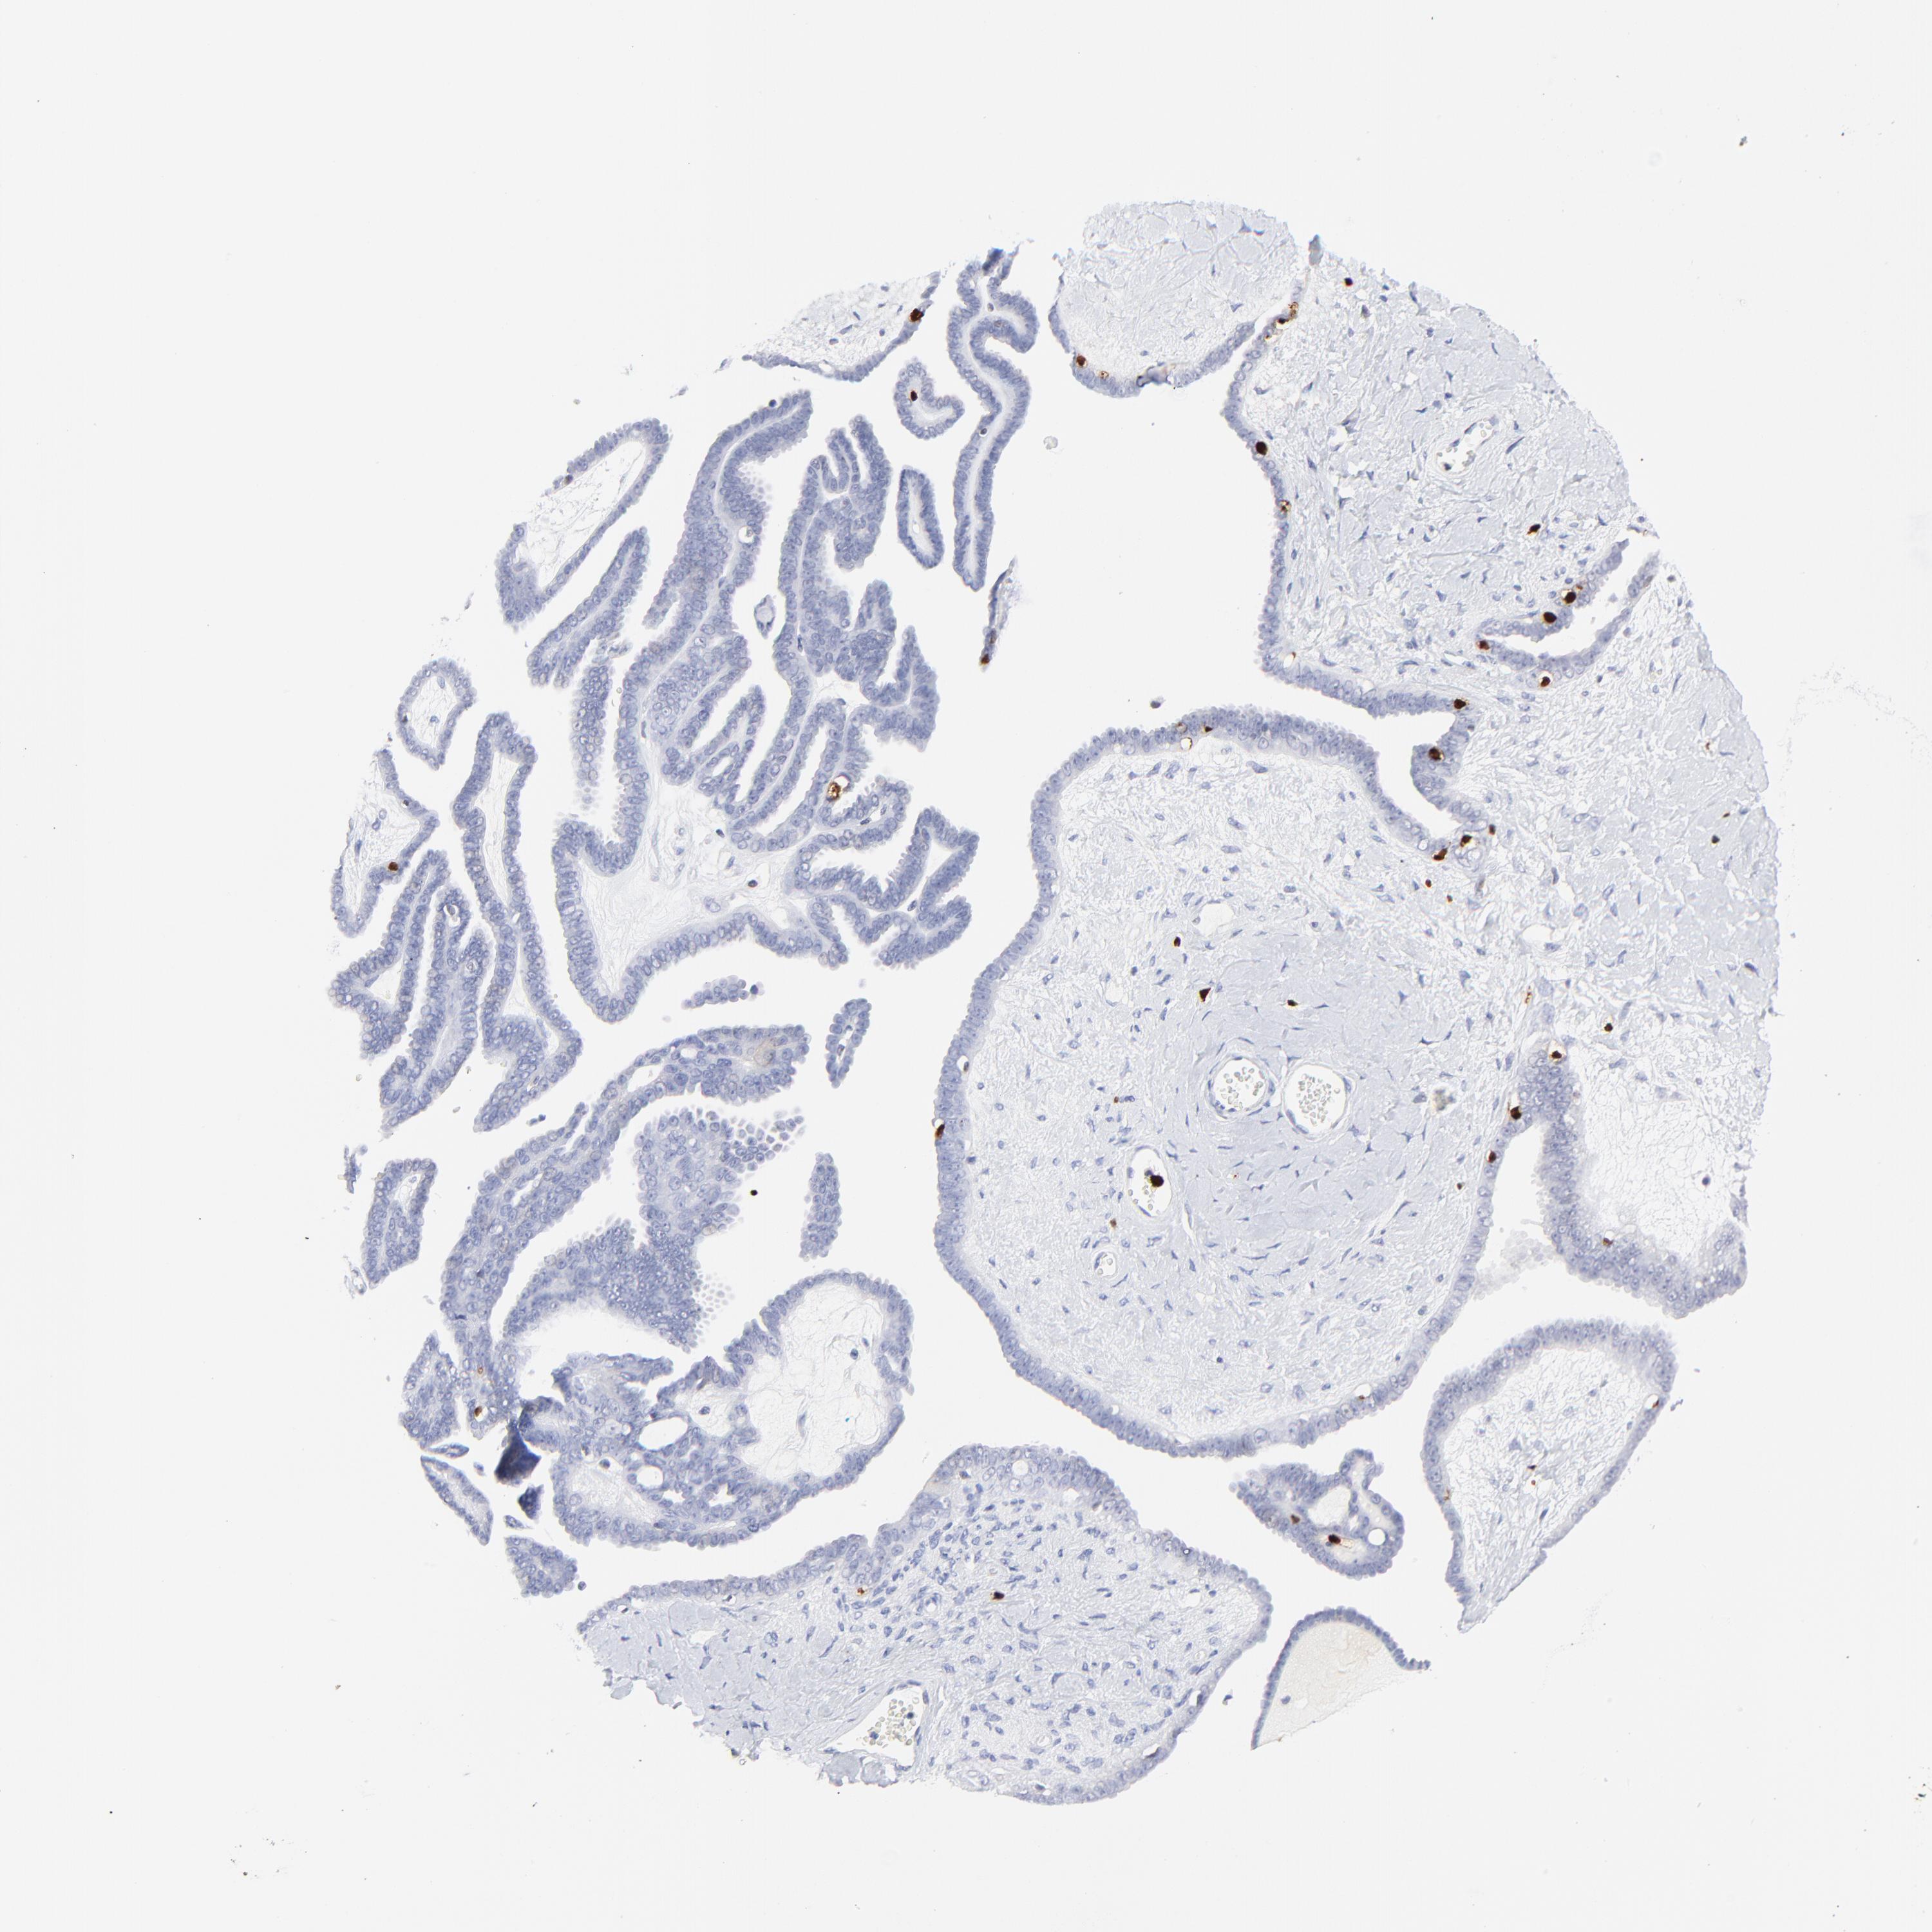

OVARIAN CANCER - Protein expressioni

A mouse-over function shows sample information and annotation data. Click on an image to view it in a full screen mode. Samples can be filtered based on level of antibody staining by selecting one or several of the following categories: high, medium, low and not detected. The assay and annotation is described here.

Note that samples used for immunohistochemistry by the Human Protein Atlas do not correspond to samples in the TCGA dataset.

Antibody stainingi

Antibody staining in the annotated cell types in the current human tissue is reported as not detected, low, medium, or high, based on conventional immunohistochemistry profiling in selected tissues. This score is based on the combination of the staining intensity and fraction of stained cells.

Each image is clickable and will lead to virtual microscopy that enables deeper exploration of all samples and also displays staining intensity scores, fraction scores and subcellular localization as well as patient and tissue information for each sample.

Antibody HPA003134

Antibody CAB002625

Cystadenocarcinoma, mucinous, NOS

Cystadenocarcinoma, serous, NOS